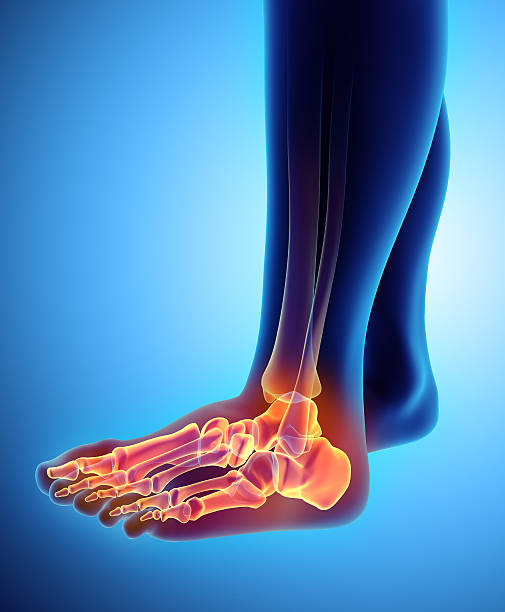

발뒤꿈치가 아픈 이유 첫 번째는 족저근막염입니다. 족저근막은 발뒤꿈치 뼈에서 시작하여 발바닥 앞쪽으로 연결되는 두껍고 강한 섬유질 띠입니다. 족저근막은 우리 몸의 중요한 역할을 하는데 아치 모양의 모양새는 우리 몸의 체중을 흡수하기 때문에 걷는 데 중요한 역할을 할 수 있습니다. 족저근막염은 이러한 족저근막에 반복되는 충격으로 근막을 둘러싸고 있는 콜라겐이 변성하면서 염증이 생긴 것을 의미합니다.

이러한 증상은 원래부터 평발이거나 걸음걸이나 생활습관 등으로 발이 변형되며 구조적으로 이상이 생겨서 문제가 생길 수도 있지만 기본적으로 하체 사용을 무리하게 하다보면 문제가 생기게 됩니다. 족저근막염 통증은 개인에 따라 다르지만 기본적으로 발뒤꿈치에 통증을 느끼게 되고 특히 아침 기상후 첫 걸음부터 통증이 나기 때문에 조기에 치료를 받는 것이 중요합니다.